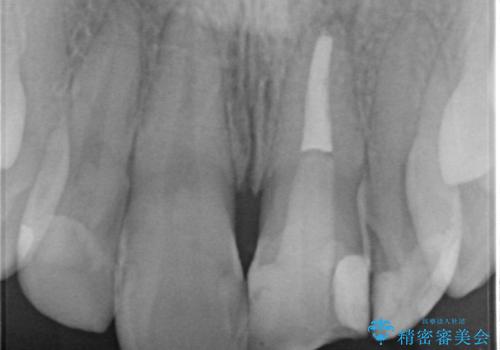

X線検査の結果、変色をきたしている歯は根尖病変が存在し、神経が失活している状態でした。

根管治療を行ったのち、セラミッククラウンで審美性を改善していきます。